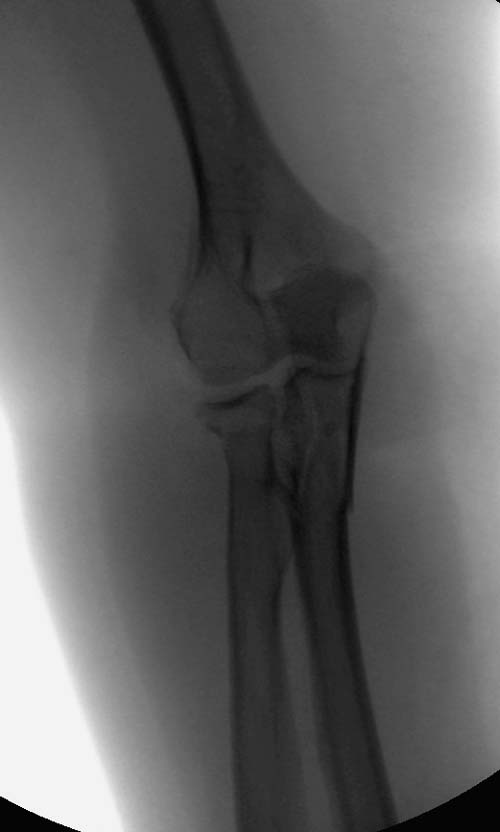

Здесь представлены несколько случаев и как видно больше больных с

серьезными повреждениями, чем изолированные..

В первом случае перелом Монтеджи, где доперационно сделано оценка

положения головки к остальным элементам под рентгеном. Учитывая

правильность взаимотношении произведена фиксация только локтевого

отростка, Второй случай, заменена на протез, и третий, кроме фиксации

головки - реконструкция capitellum латерального мыщелка.

Вложение не в текстовом формате было извлечено…

Имя     : 3 Radial head olecranon.jpg

Тип     : image/jpeg

Размер  : 24846 байтов

Описание: отсутствует

Url     : http://weborto.net:8080/pipermail/ortho/attachments/20131119/c3543de4/attachment-0009.jpg